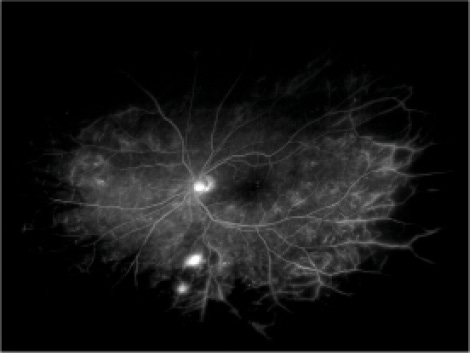

Figure 2. Widefield FA showing significant nonperfusion in the periphery.

Widefield FA

FA also comes with a widefield option (Figure 2). Advantages of this technology over traditional FA include the ability to detect peripheral neovascularization and improved ability to visualize the extent of peripheral retinal nonperfusion.14-16 It has been hypothesized that, in patients with proliferative DR or DME, VEGF production from peripheral areas of ischemia may cause a large amount of disease burden.17 By targeting panretinal photocoagulation (PRP) to these ischemic areas, VEGF may be decreased, which may help diminish the complications of DR in the eye.18,19 There is no conclusive evidence from large randomized studies to confirm whether targeted PRP based on widefield FA imaging can help improve visual outcomes.